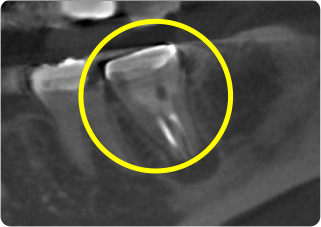

精密根管治療②

術前

| 主訴 | 奥歯で噛むと痛い |

| 治療期間/回数 | 1ヵ月、3回 |

| 価格(税込) | 88,000円(税込) |

| リスク・副作用 | 病変再発、歯根破折の可能性 |

| ポイント | う蝕検知液を用い、むし歯の取り残しが無いようにし、ラバーダム防湿を行い、無菌的に根管治療を行った。根管充填材は、殺菌作用の強い保険適応外のMTAセメントを使用した。 |